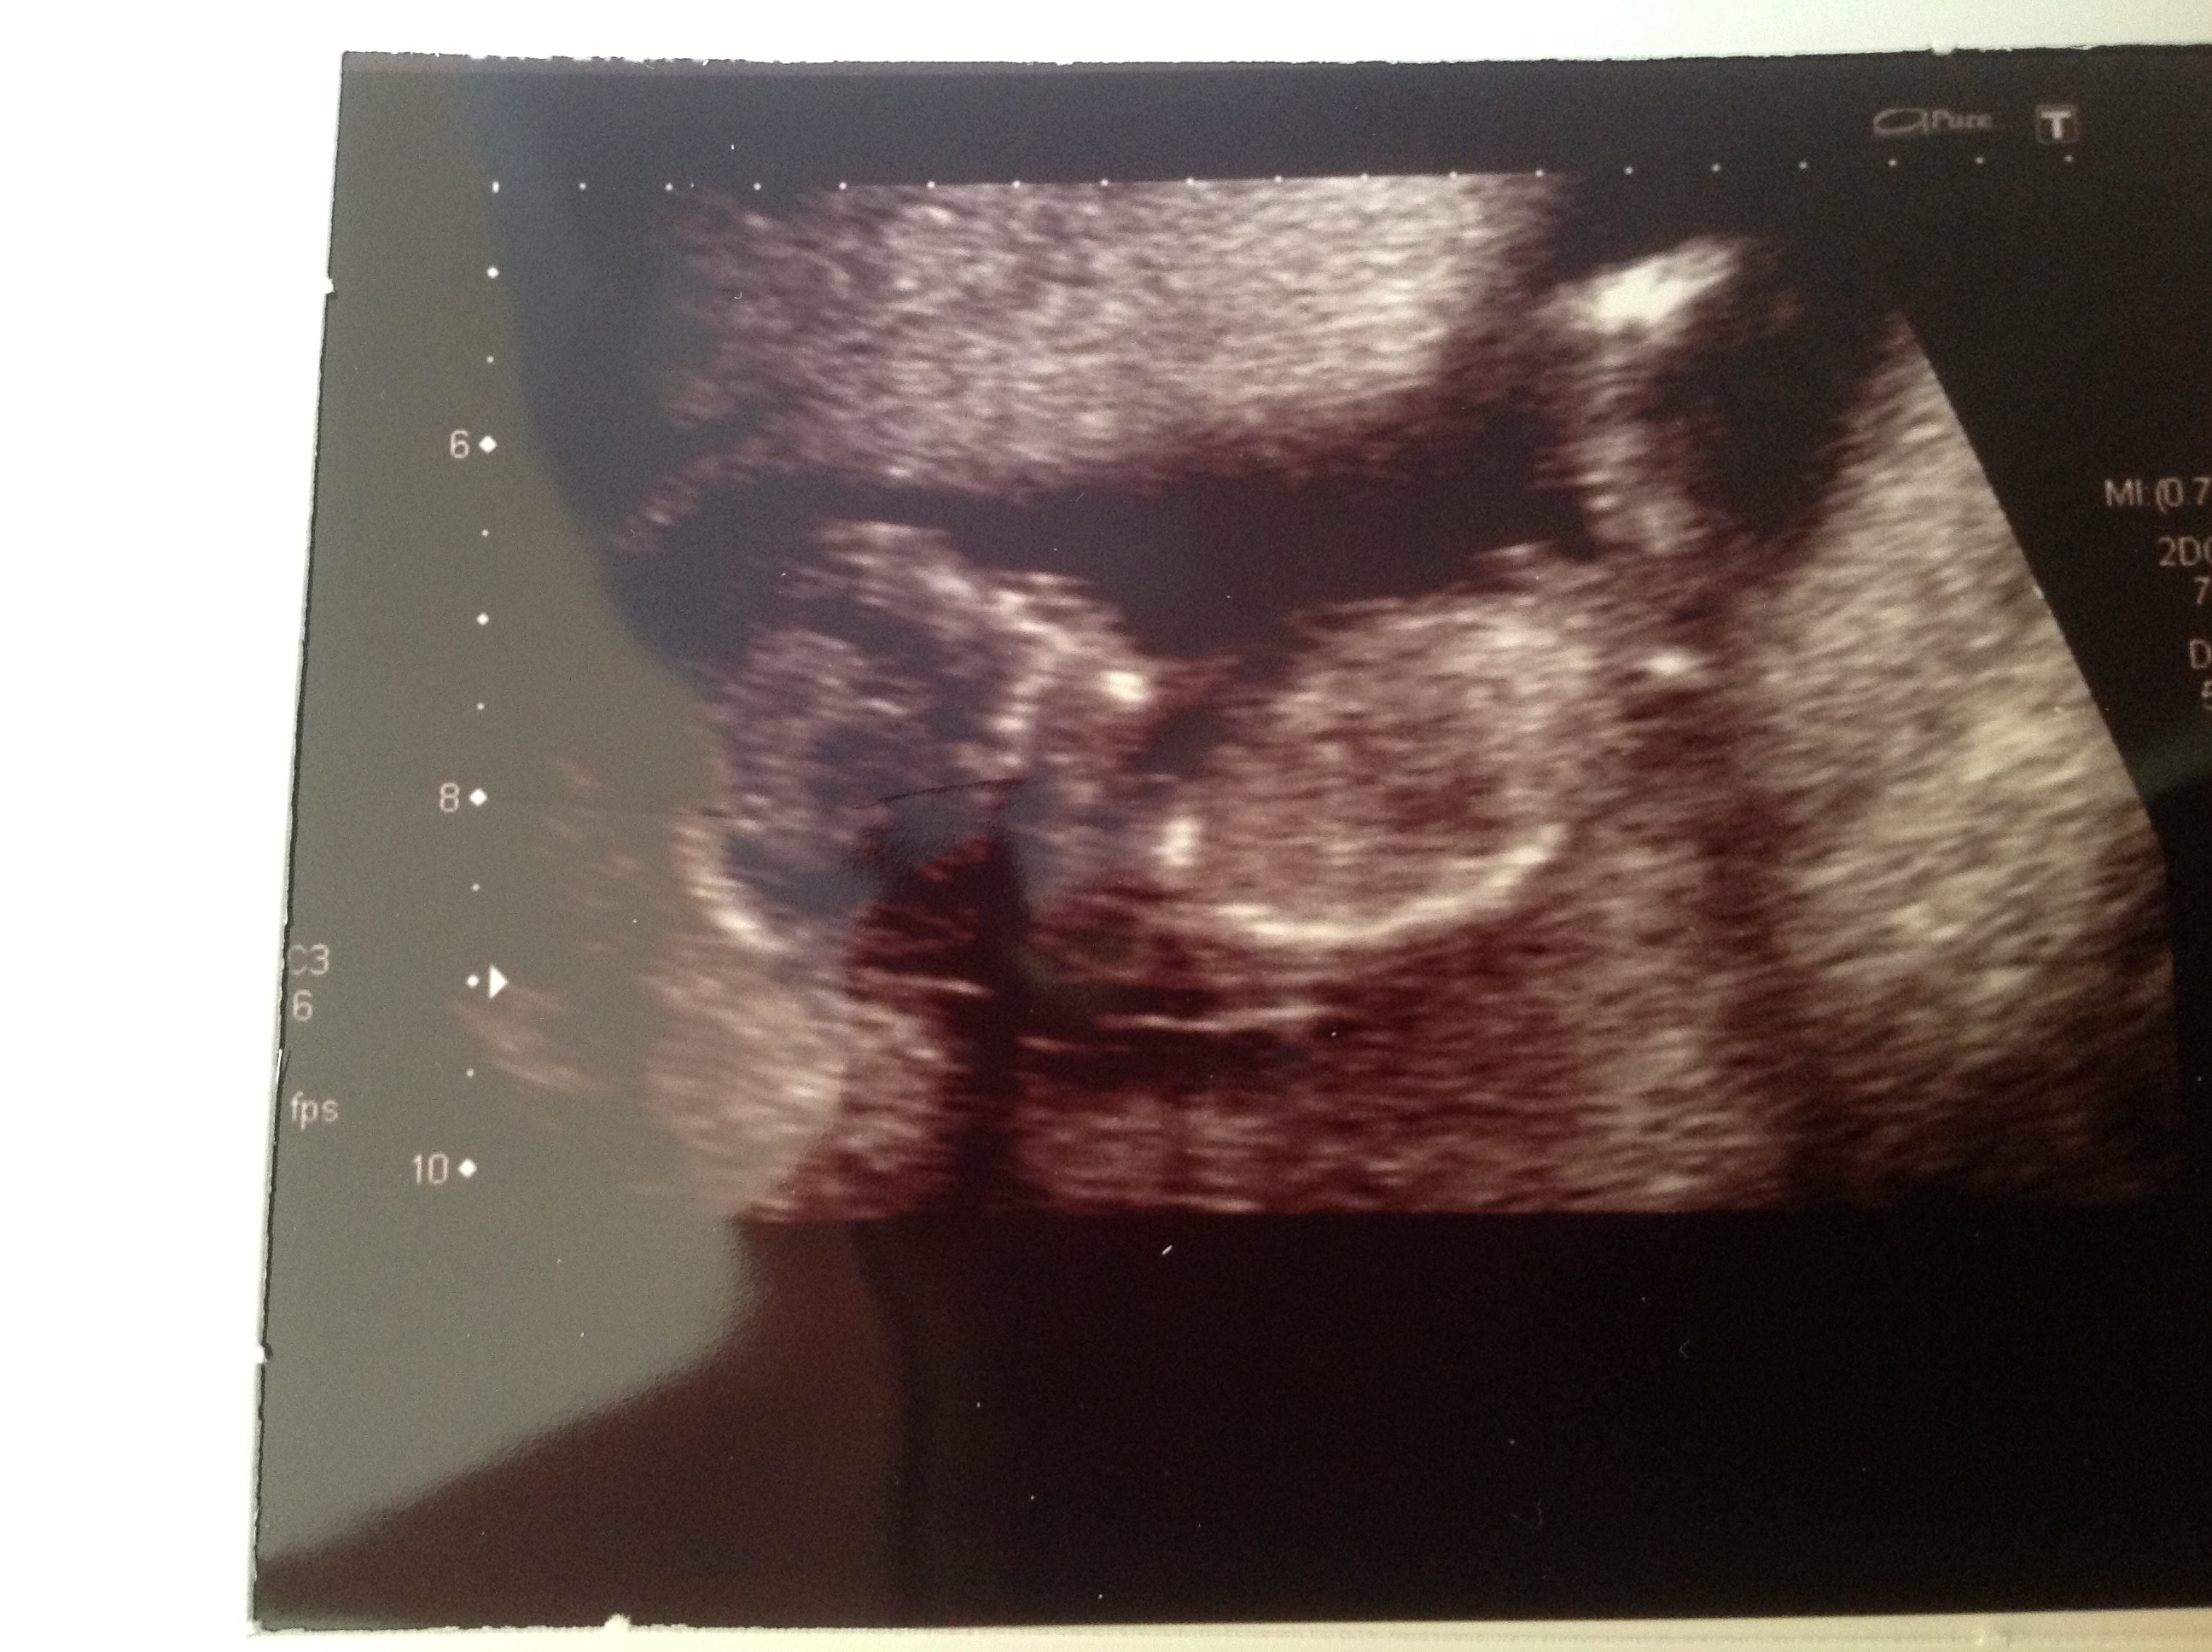

I've had a couple of scans. The first 2 pictures are at 12 weeks, 2 days. Not sure if they caught the nub?

Attachment 12284